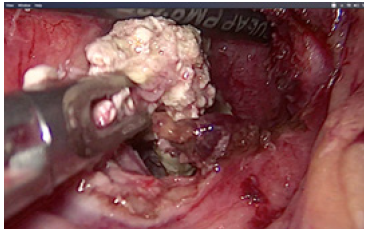

In ten cases we performed laparoscopic cholecystectomy with debridement of pancreatic necrosis. For 18 patients we explored the CBD by choledoscope and extraction of stones was done. The operation was finished with placement of T- tube drainage by laparoscopic approach. In 7 cases was accomplished percutaneous drainage of WOPN under US-control. For eight patients a two-stage procedure was applied. The first step was a placement of percutaneous biliary drainage under US-control and C-arm control. The second step was laparoscopic necrosectomy. A temporary loop ileostomy was performed in 5 cases because of bowel paralysis around the pancreas, paralytic ileus, abdominal distention and worsening of the patients’ condition. Debridement by laparoscopic access was accomplished by transgastric approach or gastrocolic access to enter the lesser sac. Applying a gentle blunt removal of necrotic tissue around pancreas, we take care of blood vessels around the pancreas, and we usually use a bipolar coagulation in case of bleeding from vital pancreatic tissues. We always take a sample from infected tissues for culture and subsequent precise antibiotic treatment (Figure 3).

Debridement of necrotic material was performed by forceps and with a laparoscopic irrigation/suction device with evacuation of infected debris (Figures 4-6).